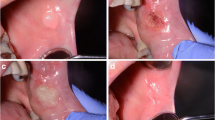

The most frequent tumors in the mouth arise from the stratified squamous oral epithelium. These are closely similar to tumors of stratified epithelium occurring at other sites and usually present no diagnostic problems. Hyperplastic fibro-epithelial lesions are the most common tumor-like swelling in the mouth and are often related to some source of chronic traumatism (e.g., cheek or tongue biting). The mucosa of these lesions is regular, smooth, pink, and usually not ulcerated, even though chronic traumatisms may cause injuries. Clinically, the lesions are painless masses of fibrous tissue usually unchanged for years [2].

(1) epithelial changes in proximity of the resection margin, evaluated from the edge of the margin to a depth of 1,000 µm. Variables evaluated include nuclear changes, (presence of picnotic, spindle-shaped and hyperchromic nuclei), cytoplasmatic and cell membrane changes (hyperchromic cytoplasm, cell fusion and/or loss of normal cell adhesion), possible intraepithelial or subepithelial loss of attachment on the basis of a cut-off value of 10% of altered tissue in the whole resection margin (Fig. 1); (2) connective tissue modifications, evaluated from the edge of the margins to a depth of 1,000 µm. Variables evaluated included carbonization (thermal necrosis), desiccation (presence of dense eosinophilic layer underlying the possible carbonization area and mainly consisting of collagen denaturation and tissue hyalinization) (Figs. 2, 3, 4); (3) presence or absence of vascular modifications, analyzed by considering a cut-off value of 10% of the above-mentioned changes in the observed area (from the edge of the margin to a depth of 1,000 µm), presence of thrombosed or collapsed blood and lymphatic vessels (including presence of intraluminal clotted erythrocytes, presence of vascular stasis (not-collapsed vessels associated to the presence of gathered erythrocytes); (4) incision morphology, subclassified into regular (presence of a linear, smooth edge for more than 90% of the whole resection margin) and irregular (presence of a rough, uneven edge for more than 90% of the whole resection margin) (Fig. 5). An overall quality score (ranging 0–4) was assigned to each incision, score “4” representing the highest quality.; (5) overall width of tissue modifications, defined as the width of tissue injuries (expressed in micrometers and separately evaluated for the epithelium, fibrous tissue and vascular structures), taking into account the minimum damage width from the resection margin. The area with the most evident damage, perpendicular to the cut margin, was chosen for the evaluation. Changes grossly exceeding the average width of the damage and presumptively associated to manipulation artifacts, were excluded from the evaluation.

When the specimens were separately analyzed according to the main size (smaller or larger than 7 mm) (Table 6), epithelial and stromal changes in histological sections less than 7 mm were more evident, independently from parameters of the laser emission used (Fig. 6). The result was extremely significant with both Chi-square and Fisher’s exact test (p < 0.0001). The differences regarding vascular changes were “quite” significant (Fisher’s exact test: p = 0.0827 and Chi-square test: p = 0.0832) (Fig. 5).